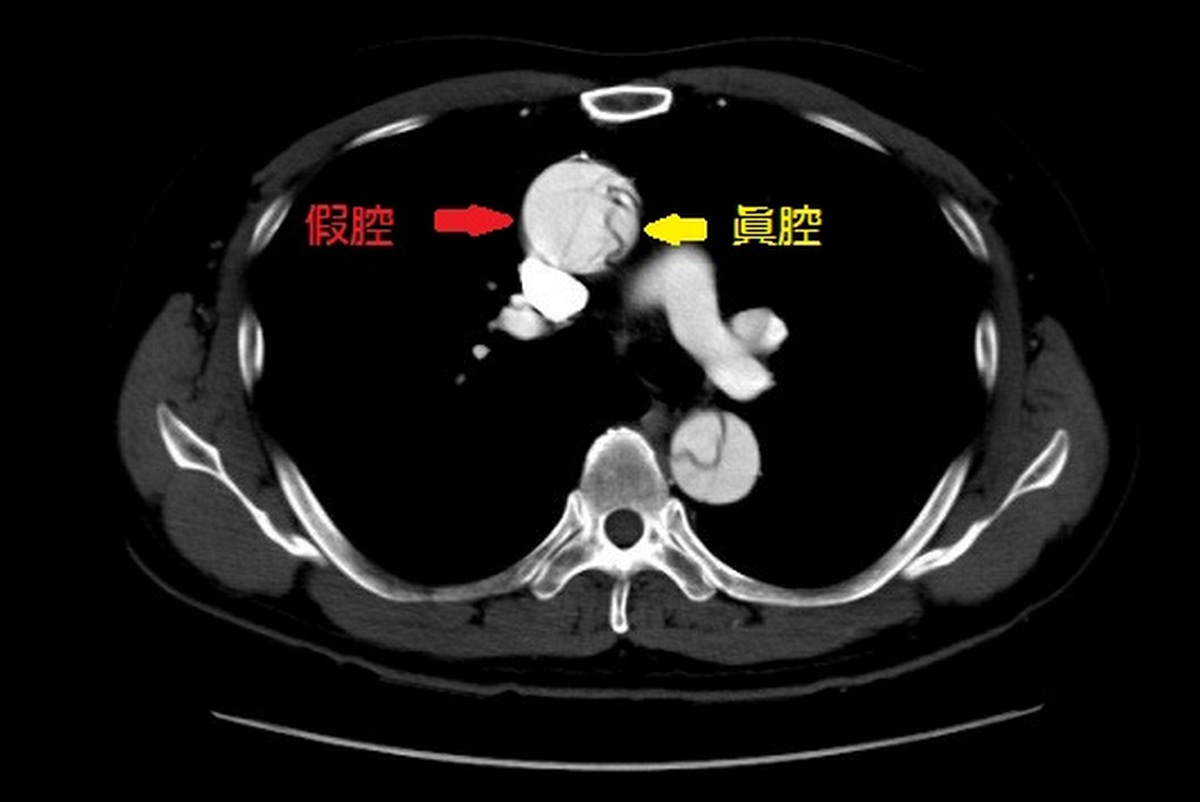

▲術前。

主動脈壁由內、中、外三層結締組織構成,正常狀態下主動脈內壁富有彈性,可一旦因高壓使動脈內層破裂產生縫隙時,血流會將主動脈撕裂成「假腔」與「真腔」兩個腔室,形成「主動脈剝離」。宋鎮宇醫師表示,主動脈剝離依史丹佛分類法分為A型及B型,A型主動脈剝離有涵蓋侵犯到昇主動脈,B型則只侵犯降主動脈。主動脈剝離發生的當下會有嚴重胸痛與後背痛、下肢無力、意識模糊甚至低血壓合併休克,死亡率較高;B型主動脈剝離雖然死亡率較低,但卻也容易影響腎臟、腸道與下肢血流,產生腎功能受損、下肢缺血等併發症。B型主動脈剝離以藥物控制血壓與疼痛,追蹤觀察即可,若有近一步變化或擴大才需以手術治療。